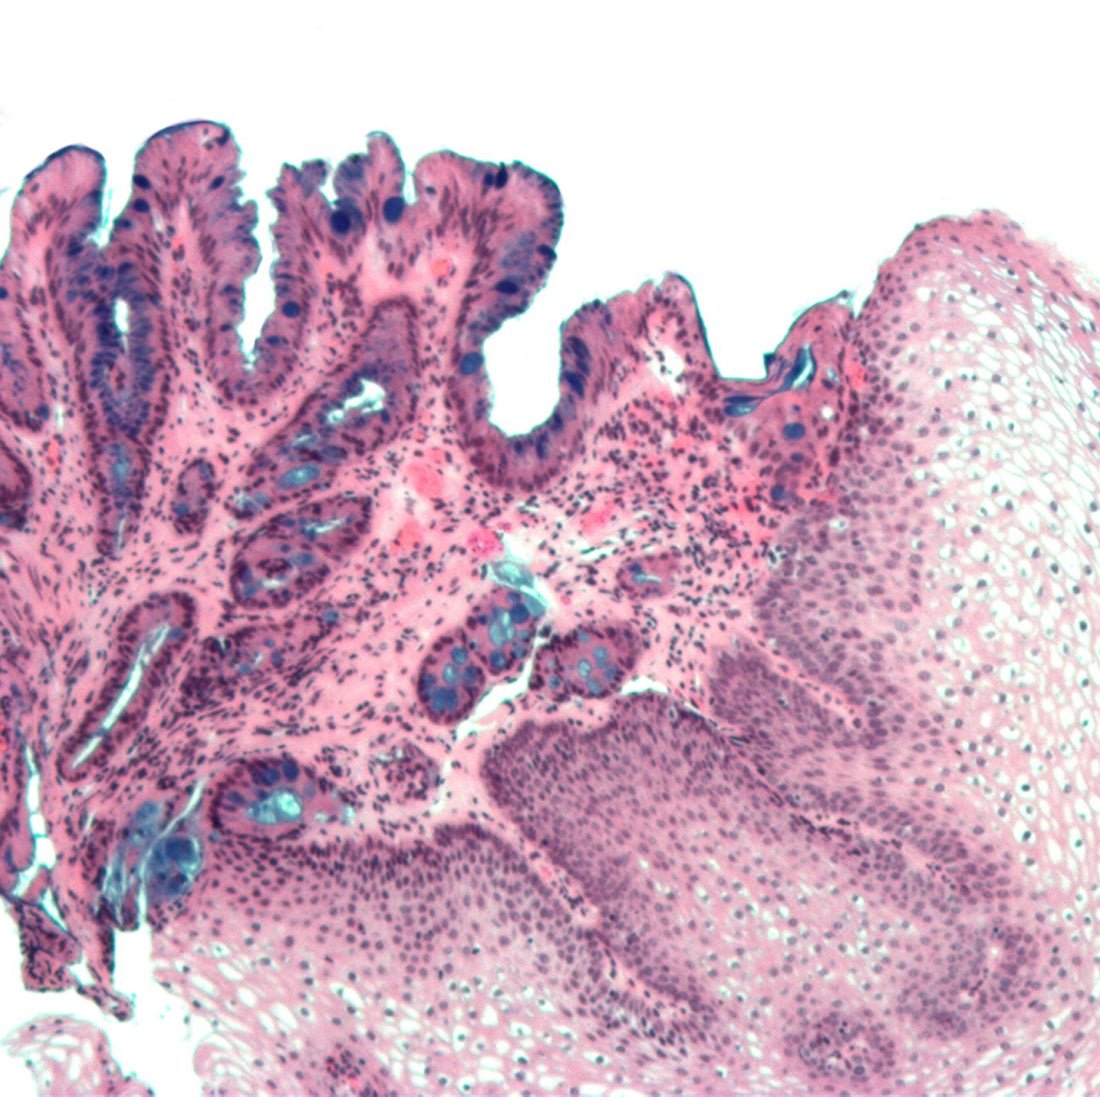

This is a combined method utilizing the properties of both PAS and Alcian blue pH 2.5 methods to demonstrate the full complement of tissue proteoglycans. Alcian Blue pH 2.5 stains the acid mucins blue while PAS stains the neutral mucins pink to red.

- Acid mucins- blue

- Neutral mucins and other PAS positive tissue elements- pink to red

- Acid and neutral mucins mixtures- purple